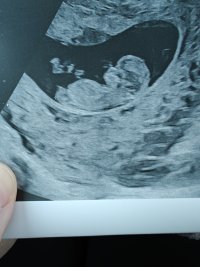

Nub-teorian mukaan sukupuolen voi määrittää jo nt-ultrassa genitaalikyhmyn asennon perusteella. Voit lukea aiheesta lisää täältä.

Kiinnostaako teitä sukupuolen määrittäminen kyseisen teorian avulla? Katsotteko ultrakuvia sillä silmällä?